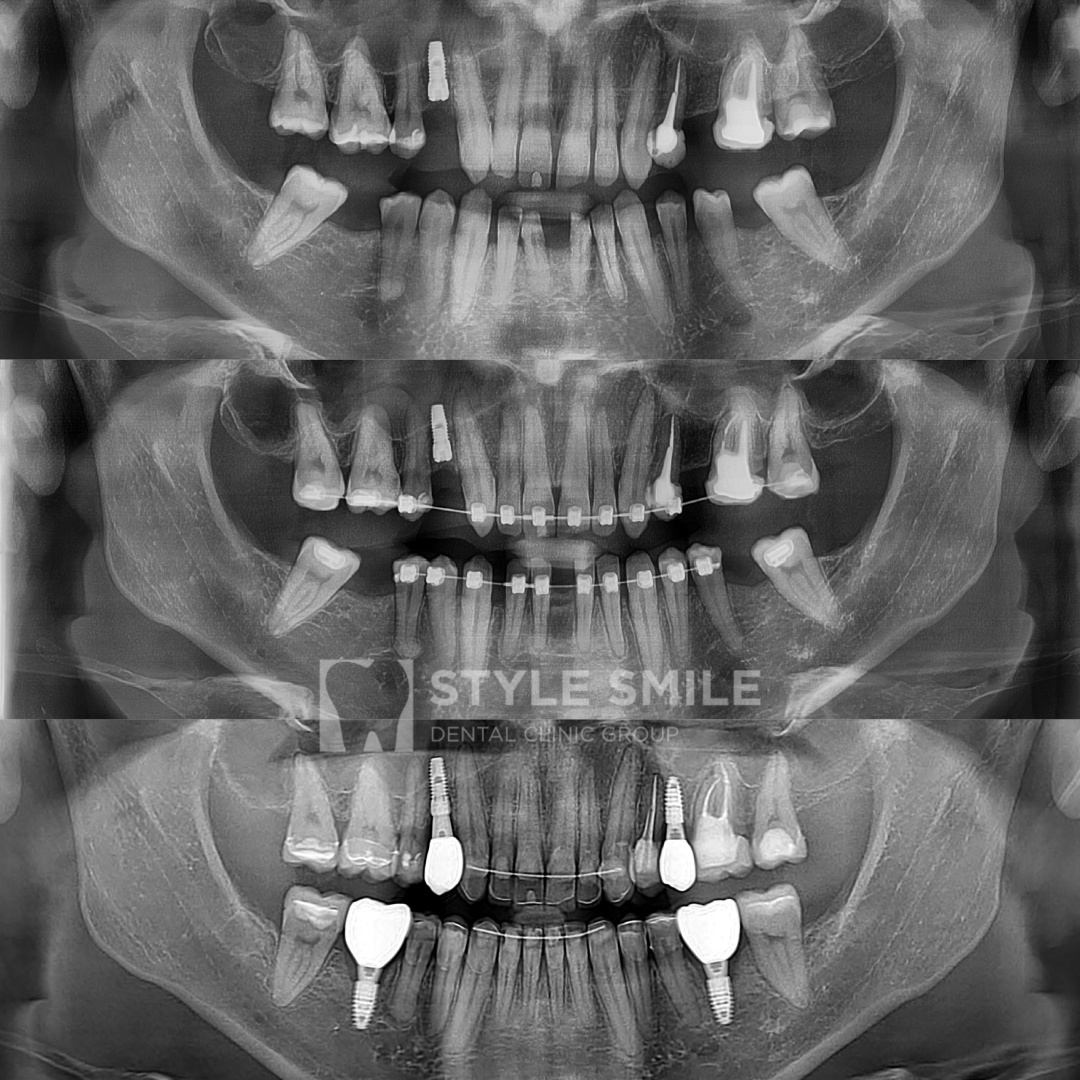

1 - до лечения,

2 - во время лечения,

3 - после окончания лечения

1 - до лечения, 2 - во время лечения, 3 - после окончания лечения